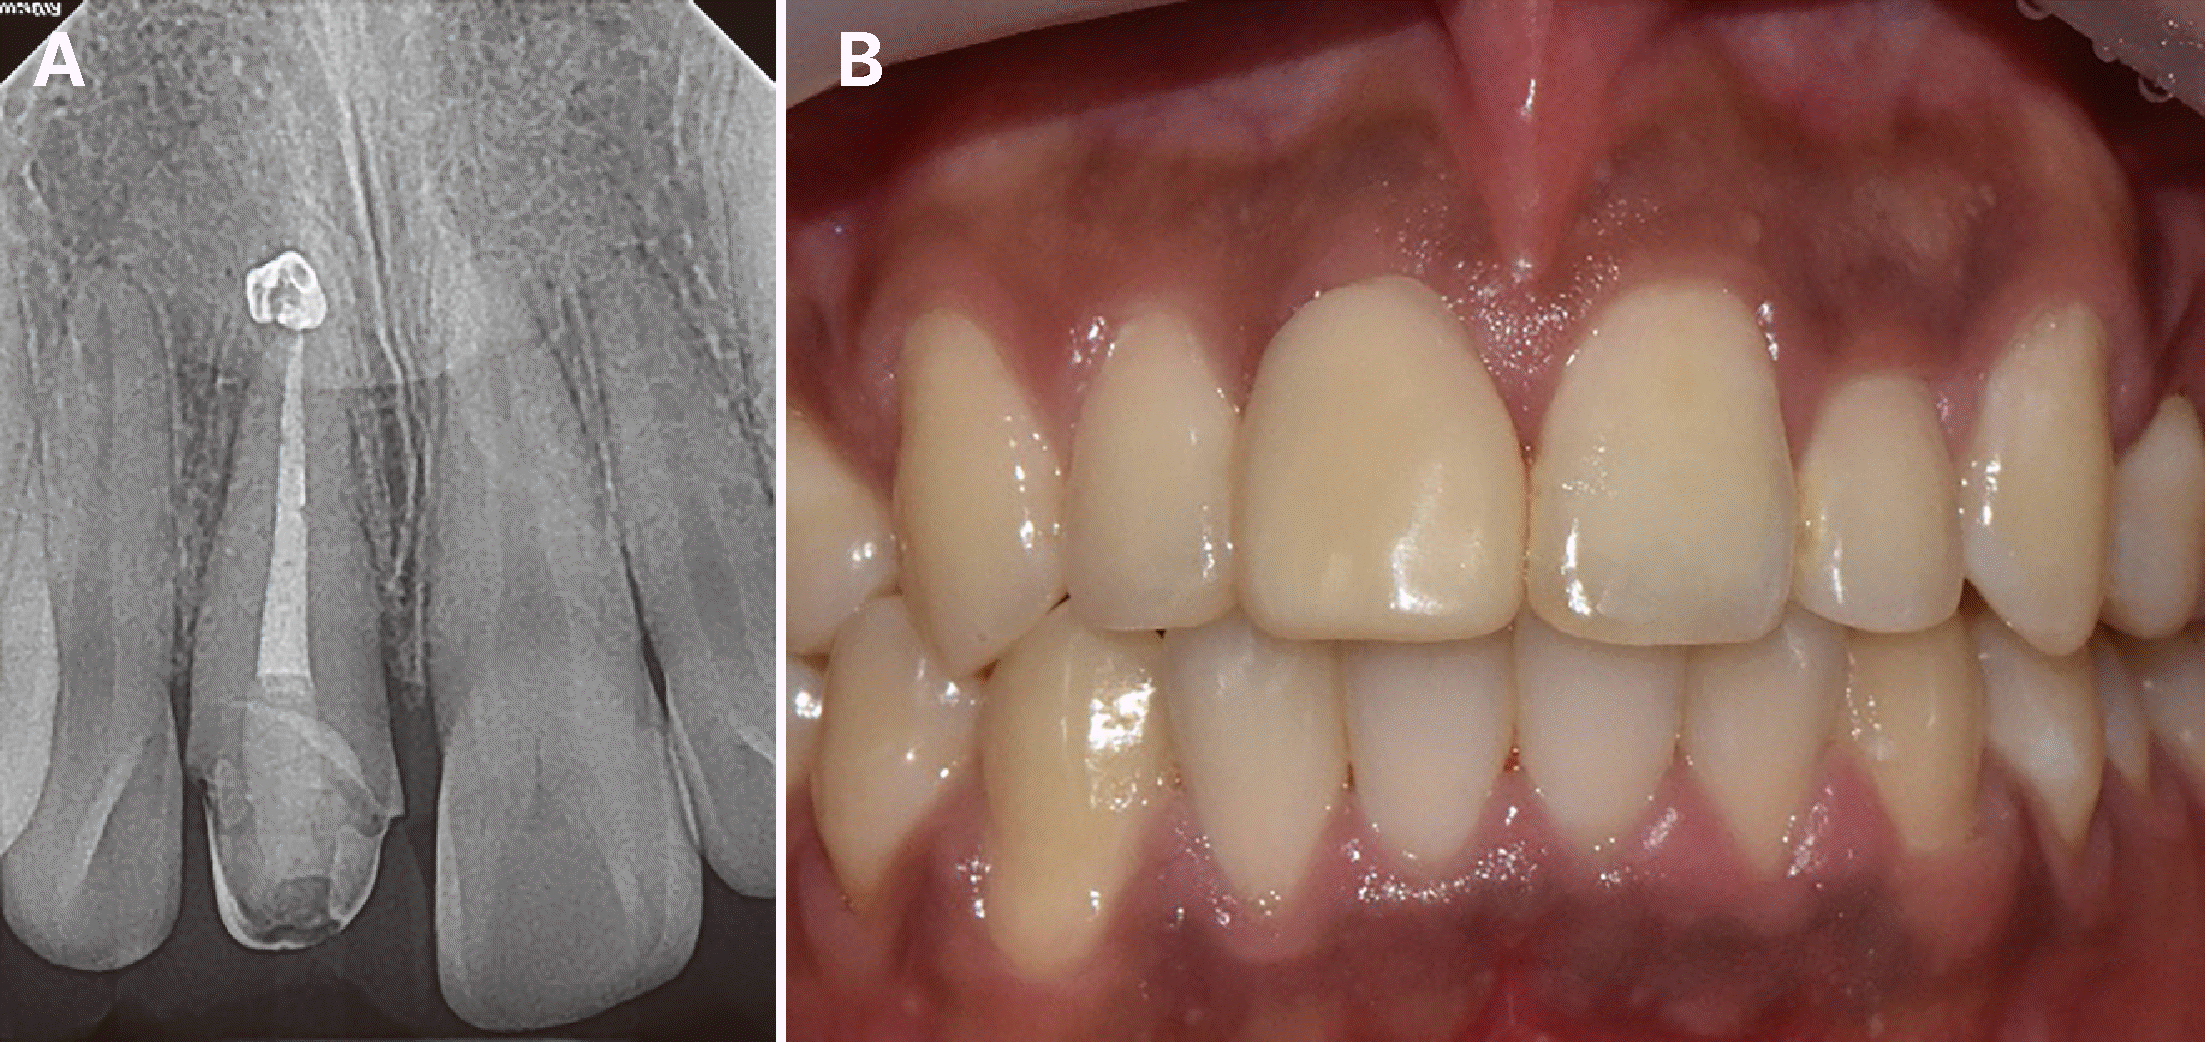

28세 남자 환자가 3일 전 넘어져서 치아가 부러졌다는 주소로 내원하였다. 외상 발생 다음날 개인 치과에서 파절편 제거, 발수 및 근관 성형 시행 후 본과로 의뢰되었으며 임상 검사 및 방사선 검사 상 우측 상악 중절치의 치수강을 침범한 치관-치근 파절이 관찰되었다. 파절선은 협면 절단측 1/3 경계에서 시작하여 구개측 치은연하로 연장되었으며 5 - 6 mm의 치주낭 깊이를 보였다. 동요도는 없었으나 잔존 치관부에 균열선이 관찰되었으며 타진 및 촉진에 통증을 호소하였다(Fig. 1). 이에 따라 우측 상악 중절치의 복잡 치관-치근 파절로 진단하였다. 첫 내원일에 추가적인 근관 성형과 세정을 시행하였다. 해당 치아에 러버댐 격리를 위한 클램프를 직접 적용하면 통증을 유발할 수 있기 때문에 상악 양측 견치에 클램프를 적용하여 격리를 시행하였다. 근관치료를 위한 국소마취를 시행하지 않았음에도 근관 내 기구조작에 통증을 호소하지 않았다. 페이퍼 포인트를 적용하였을 때 근관 건조가 잘 되는 것을 확인하고 수산화칼슘 첩약 후 임시가봉을 시행하였다. 환자가 심미적 불편감을 호소하여 협측 치관 파절 부위에 레진 수복을 추가적으로 시행하였다. 치아에 대한 전반적인 평가를 시행한 후 환자에게 구개측 치은 연하로 연장된 파절선에 대한 처치가 필요하며 이를 위해 교정적 정출술과 외과적 정출술 중에 선택할 수 있음과 각각의 방법, 기간 및 장단점에 대해 설명하였다. 환자는 치료를 단기간에 끝내야 하고, 재발의 위험성이 적은 방법을 선호하여 외과적 정출술을 시행하기로 결정하였다. 또한, 치아의 구개측 파절선이 협측에 비해 치은연하로 연장된 형태이기 때문에 외과적 정출술을 시행할 때 180°회전 식립하여 협설측 치조골의 높이 차이를 이용해 정출량을 감소시키고 치근 길이를 더 확보할 수 있음을 설명하였다.

Fig. 1

(A) Preoperative radiograph of maxillary right central incisor. (B) Photograph of palatal probing depth on maxillary right central incisor.